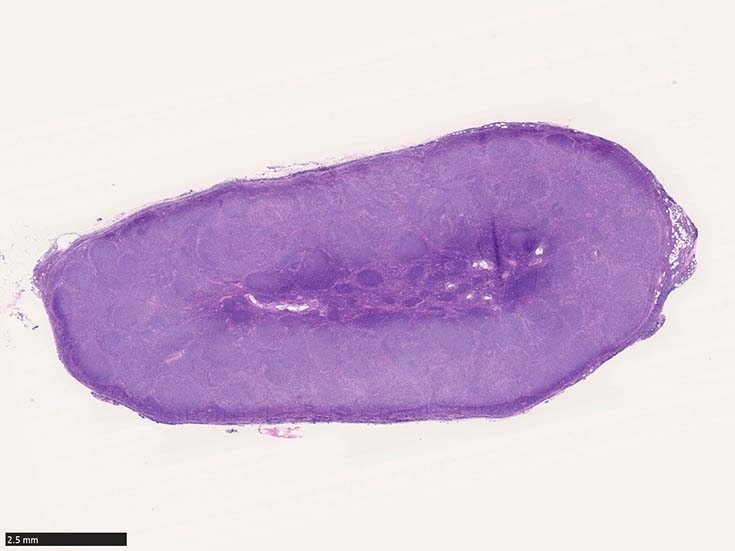

SM02-HEhpf03.jpg

濾胞増殖pattern

低倍率像で濾胞は濾胞間組織にくらべ明るくみえる症例がほとんど。これは小型リンパ球よりやや大型で蒼白な腫瘍細胞が増殖するため。

濾胞が濾胞間組織より暗く見えるreverse patternの症例が認められる。

腫瘍性濾胞は均等にリンパ節全体に分布する。辺縁洞は閉塞され,時に被膜外へ浸潤する。